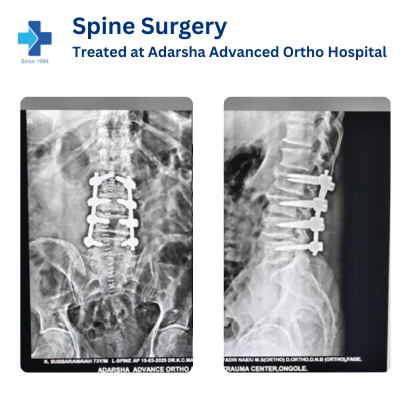

Spine Surgery

Spine surgery is a procedure performed to correct problems related to the spinal cord and vertebrae. It is usually recommended when back or neck pain becomes severe and doesn't improve with medicines or physical therapy.

This surgery helps treat conditions like slipped disc, spinal stenosis, spine fractures, or nerve compression. The goal is to reduce pain, restore movement, and improve the patient's overall quality of life. Advanced techniques ensure a safe and faster recovery.